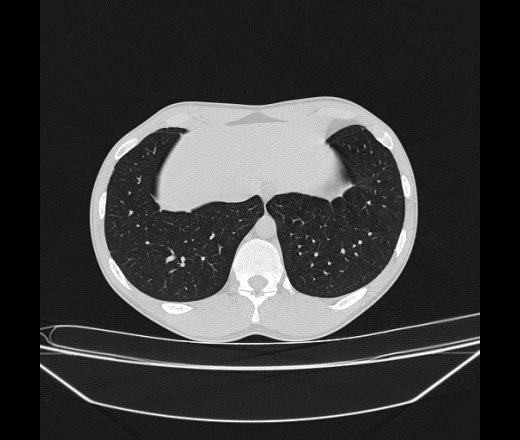

Молодой парень 18 лет, призывник, при прохождении ФЛС на верхушек левого легкого выявили очаги средней интснисвности с нечеткими контурами, тяжи. Сделали бок и томограммы 6-7-8. Везде описывают как очаговый твс. Вижу только перибронхиальный фиброз. Что за изменения в бронхах, указано нижи стрелками, тоже перибронхиальный?

Не стал бы говорить об очагах. Акцентировал бы не на фиброзе, а на тракционных бронхоэктазах. Не обязательно они результат tbc бронхов, но проверить не помешает.

Иван, пациент ведь уже "направлен с ОПТД", так?surprise Возвращайте его назад с заключением о возможном микобактериозе. Остаточные поствоспалительные ( посттуберкулёзные?) в дифряд.Очаговый твс с неясной активностью они уже себе "нарисовали", как я поняла.

+1 за микобактериоз.